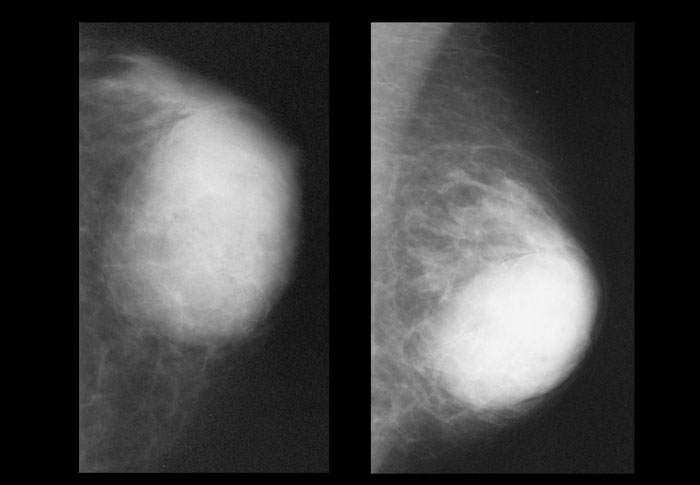

( A ) Синдром Поланда с минимальной мускулатурой в подключичной области, отсутствием передней подмышечной складки и гипоплазией молочной железы в адекватном месте (Перепечатано с разрешения Caouette-Laberge L, Bortoluzzi P. Коррекция асимметрии груди у подростков. В: Hall Findley E, Evans GRD, редакторы Эстетическая и реконструктивная хирургия груди.Филадельфия, Пенсильвания: Saunders Elsevier; 2010: 601–629). ( B ) Через два года после пересадки мышц и увеличения груди с помощью подмышечного грудного имплантата, вставленного во время пересадки мышц, обратите внимание на шрам на проксимальной части руки для повторного прикрепления сухожилия к плечевой кости. ( C ) Минимальная деформация спины после переноса широчайшей мышцы (круглый пронатор остается для задней подмышечной складки) (Перепечатано с разрешения Caouette-Laberge L, Bortoluzzi P. Коррекция асимметрии груди у подростков.В: Холл Финдли Э., Эванс GRD, ред. Эстетическая и реконструктивная хирургия груди. Филадельфия, Пенсильвания: Saunders Elsevier; 2010: 601–629). ( D ) Срединно-грудной рубец через 2 месяца после переноса широчайшей мышцы (перепечатано с разрешения Caouette-Laberge L, Bortoluzzi P. Коррекция асимметрии груди у подростков. В: Hall Findley E, Evans GRD, eds. Эстетическая и реконструктивная хирургия груди , Филадельфия, Пенсильвания: Saunders Elsevier, 2010: 601–629).

( C ) Минимальная деформация спины после переноса широчайшей мышцы (круглый пронатор остается для задней подмышечной складки) (Перепечатано с разрешения Caouette-Laberge L, Bortoluzzi P. Коррекция асимметрии груди у подростков.В: Холл Финдли Э., Эванс GRD, ред. Эстетическая и реконструктивная хирургия груди. Филадельфия, Пенсильвания: Saunders Elsevier; 2010: 601–629). ( D ) Срединно-грудной рубец через 2 месяца после переноса широчайшей мышцы (перепечатано с разрешения Caouette-Laberge L, Bortoluzzi P. Коррекция асимметрии груди у подростков. В: Hall Findley E, Evans GRD, eds. Эстетическая и реконструктивная хирургия груди , Филадельфия, Пенсильвания: Saunders Elsevier, 2010: 601–629).